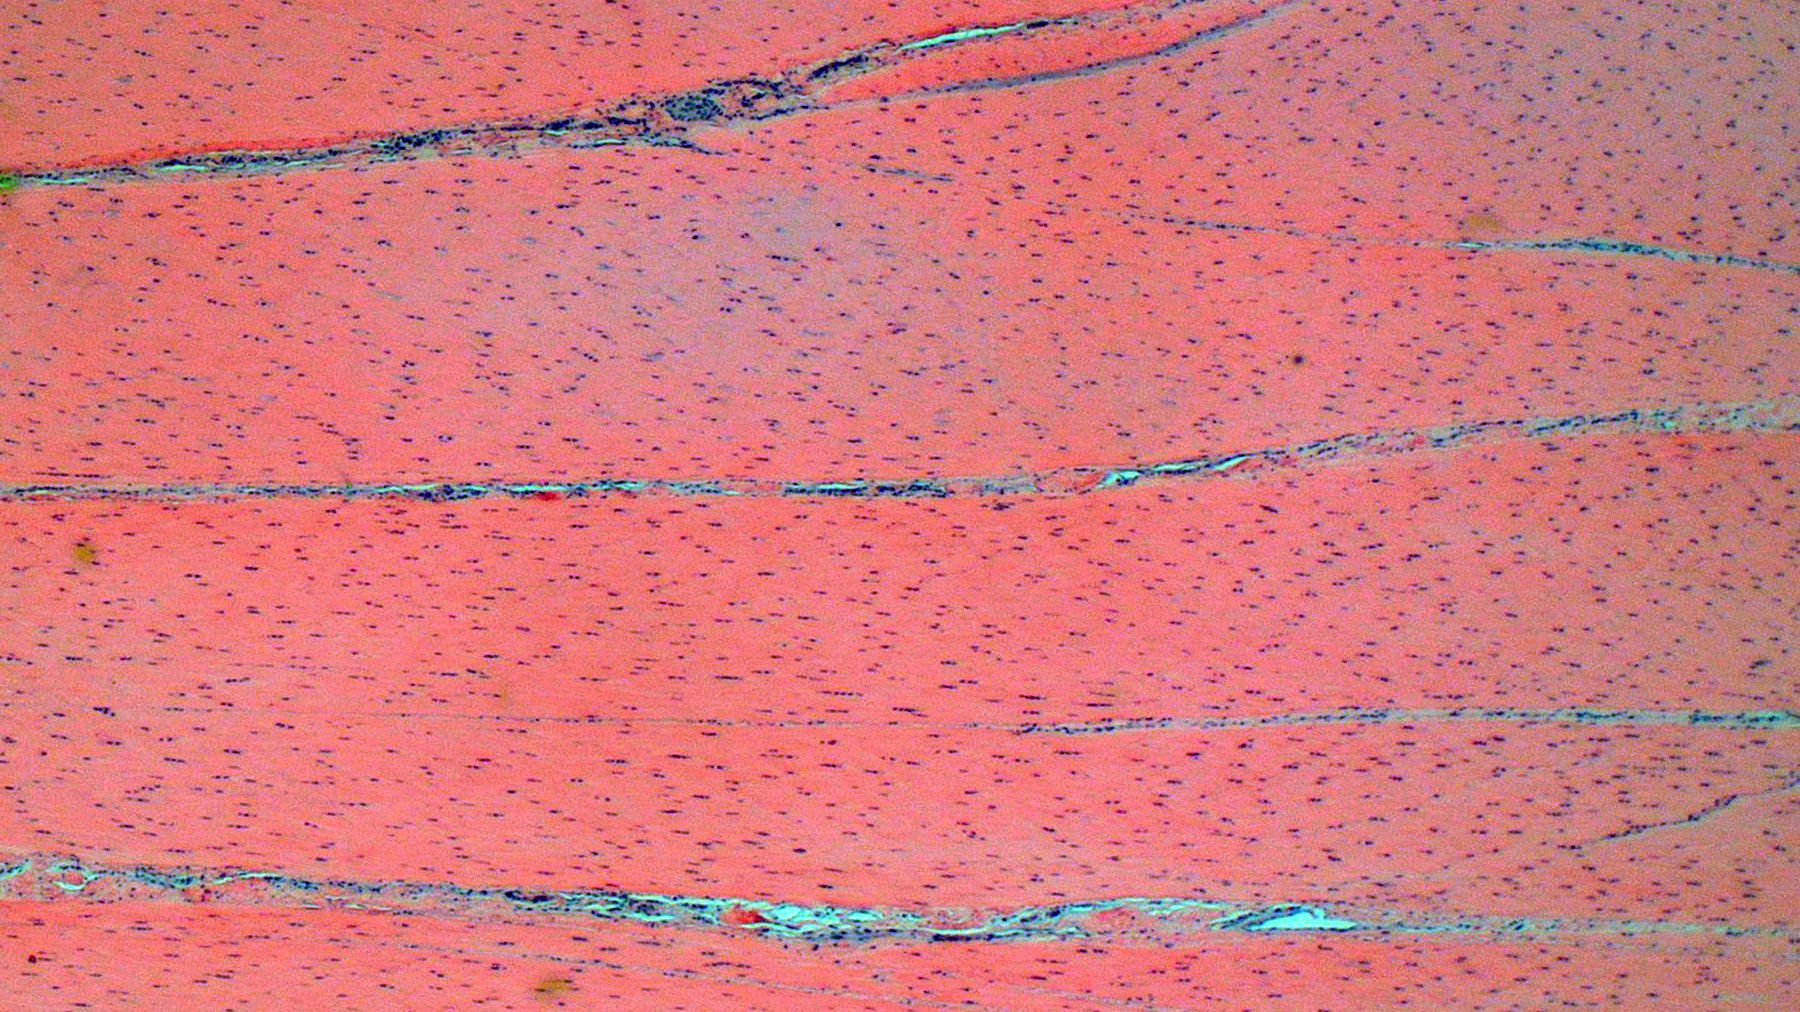

Suspensory ligament, right rear branch. Compared to a branch of the clinically normal right front suspensory ligament, collagen fibers are irregular and often form intersecting or divergent bundles. In many areas, there are fewer fibroblasts among collagen fibers than in the normal control. Throughout the tissue, wavy tendrils of pale basophilic, Alcian blue-positive matrix dissect between collagen bundles. Similar material surrounds increased numbers of variably sized, dilated and tortuous blood vessels. These vessels have thin walls and are lined by plump endothelial cells, and are often surrounded by loosely arranged stellate cells. In other areas, there is chondroid metaplasia, with clustered and individual chondrocyte-like cells in lacunae surrounded by amorphous, pale basophilic matrix, which is sometimes faintly mineralized. There is rare hemorrhage.Contributor's Morphologic Diagnoses:

The terms degenerative suspensory ligament desmitis (DSLD) and suspensory ligament degeneration (SLD) are used somewhat synonymously, with DSLD often used to describe horses with a clinical diagnosis of suspensory ligament degeneration, and SLD used to describe histologic findings in the suspensory ligaments of horses that may or may not have a clinical diagnosis of DSLD. DSLD causes chronic, progressive multi-limb lameness of variable severity, often recognized by enlarged, hyperextended or dropped fetlocks.8 The rear limbs are typically more affected.3,8 In addition, the terms suspensory ligament desmitis or suspensory ligament desmopathy may be used to describe any of a variety of clinically or ultrasonographically detected injuries anywhere along the length of the suspensory ligament.3 Histology is rarely performed in these cases, especially in the acute phase, and it is unclear if these injuries are related to degenerative changes.3Histologic changes in SLD/DSLD include loss of longitudinal arrangement of collagen fibers, proteoglycan accumulation, presence of chondrocytes, hemorrhage, vascular proliferation, and widened interstitial connective tissue septa.4,6 Despite the use of the term desmitis, inflammatory cells are not present.4 These changes are reported to be more severe in the branches of the suspensory ligament than in the body or origin of the ligament.3,5

The major histologic findings within ligaments suffering from SLD include loss of longitudinal arrangement of collagen fibers (disorganization), proteoglycan accumulation (increased ground substance), presence of chondrocytes (chondroid metaplasia), hemorrhage, vascular proliferation, widened interstitial connective tissue septae, and a lack of inflammatory cells.8 As this disease develops, regardless of cause, degenerating collagen fascicles blend together and there is either death of the tenocytes/ligamentocytes or metaplasia of tenocytes/ligamentocytes into chondrocytes. Fibrosis develops within and around the ligament and is usually associated with hypertrophied tenocytes/ligamentocytes. These areas are generally interpreted as failed attempts at repair.